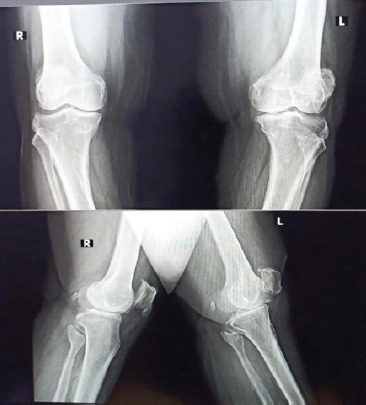

Case report: We report the case of a 67-year-old female with grade 4 osteoarthritis of the left knee who underwent TKR following the failure of conservative management. Postoperatively, the patient developed stiffness and a reduced range of motion. Radiographic imaging at 5 weeks showed haziness in the anterior aspect of the femur at the upper border of the femoral implant, with gradual progression to distinct ossification by 3 months.